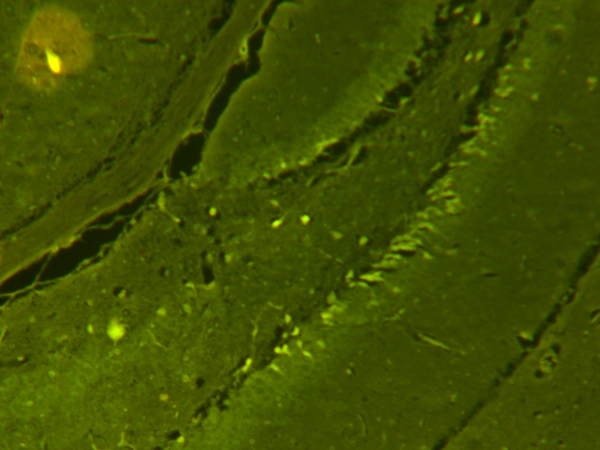

ایمونوهیستوشیمی و ایمنوفلورسنت (IHC) برای تعیین آنتی ژنی خاص در بافت بکار میرود.

اساس ایمونوهیستوشیمی، ردیابی آنتی ژن ها در برش های بافتی با استفاده از آنتی بادی های کنژوگه شده با مواد فلئوروسنت، آنزیم ها و عناصر رادیواکتیو می باشد که پس از اتصال آنتی بادی کنژوگه شده به آنتی ژن هدف در سطح بافت و تولید یک محصول رنگی طی واکنش هیستوشیمی با میکروسکوپ نوری یا میکروسکوپ فلوروکروم و با نور ماوراء بنفش (UV) می توان محصول رنگی را که در واقع محل بیان آنتی ژن موردنظر است، تشخیص داد.

برای تصویر برداری از میکروسکوپهای Inverted Microscope - IM-3 Optika ITALY- و Fluorescence Microscope - BM-600 LED - Axiom – Germany و Olympus BX50 استفاده میشود

نمونه های انجام شده: